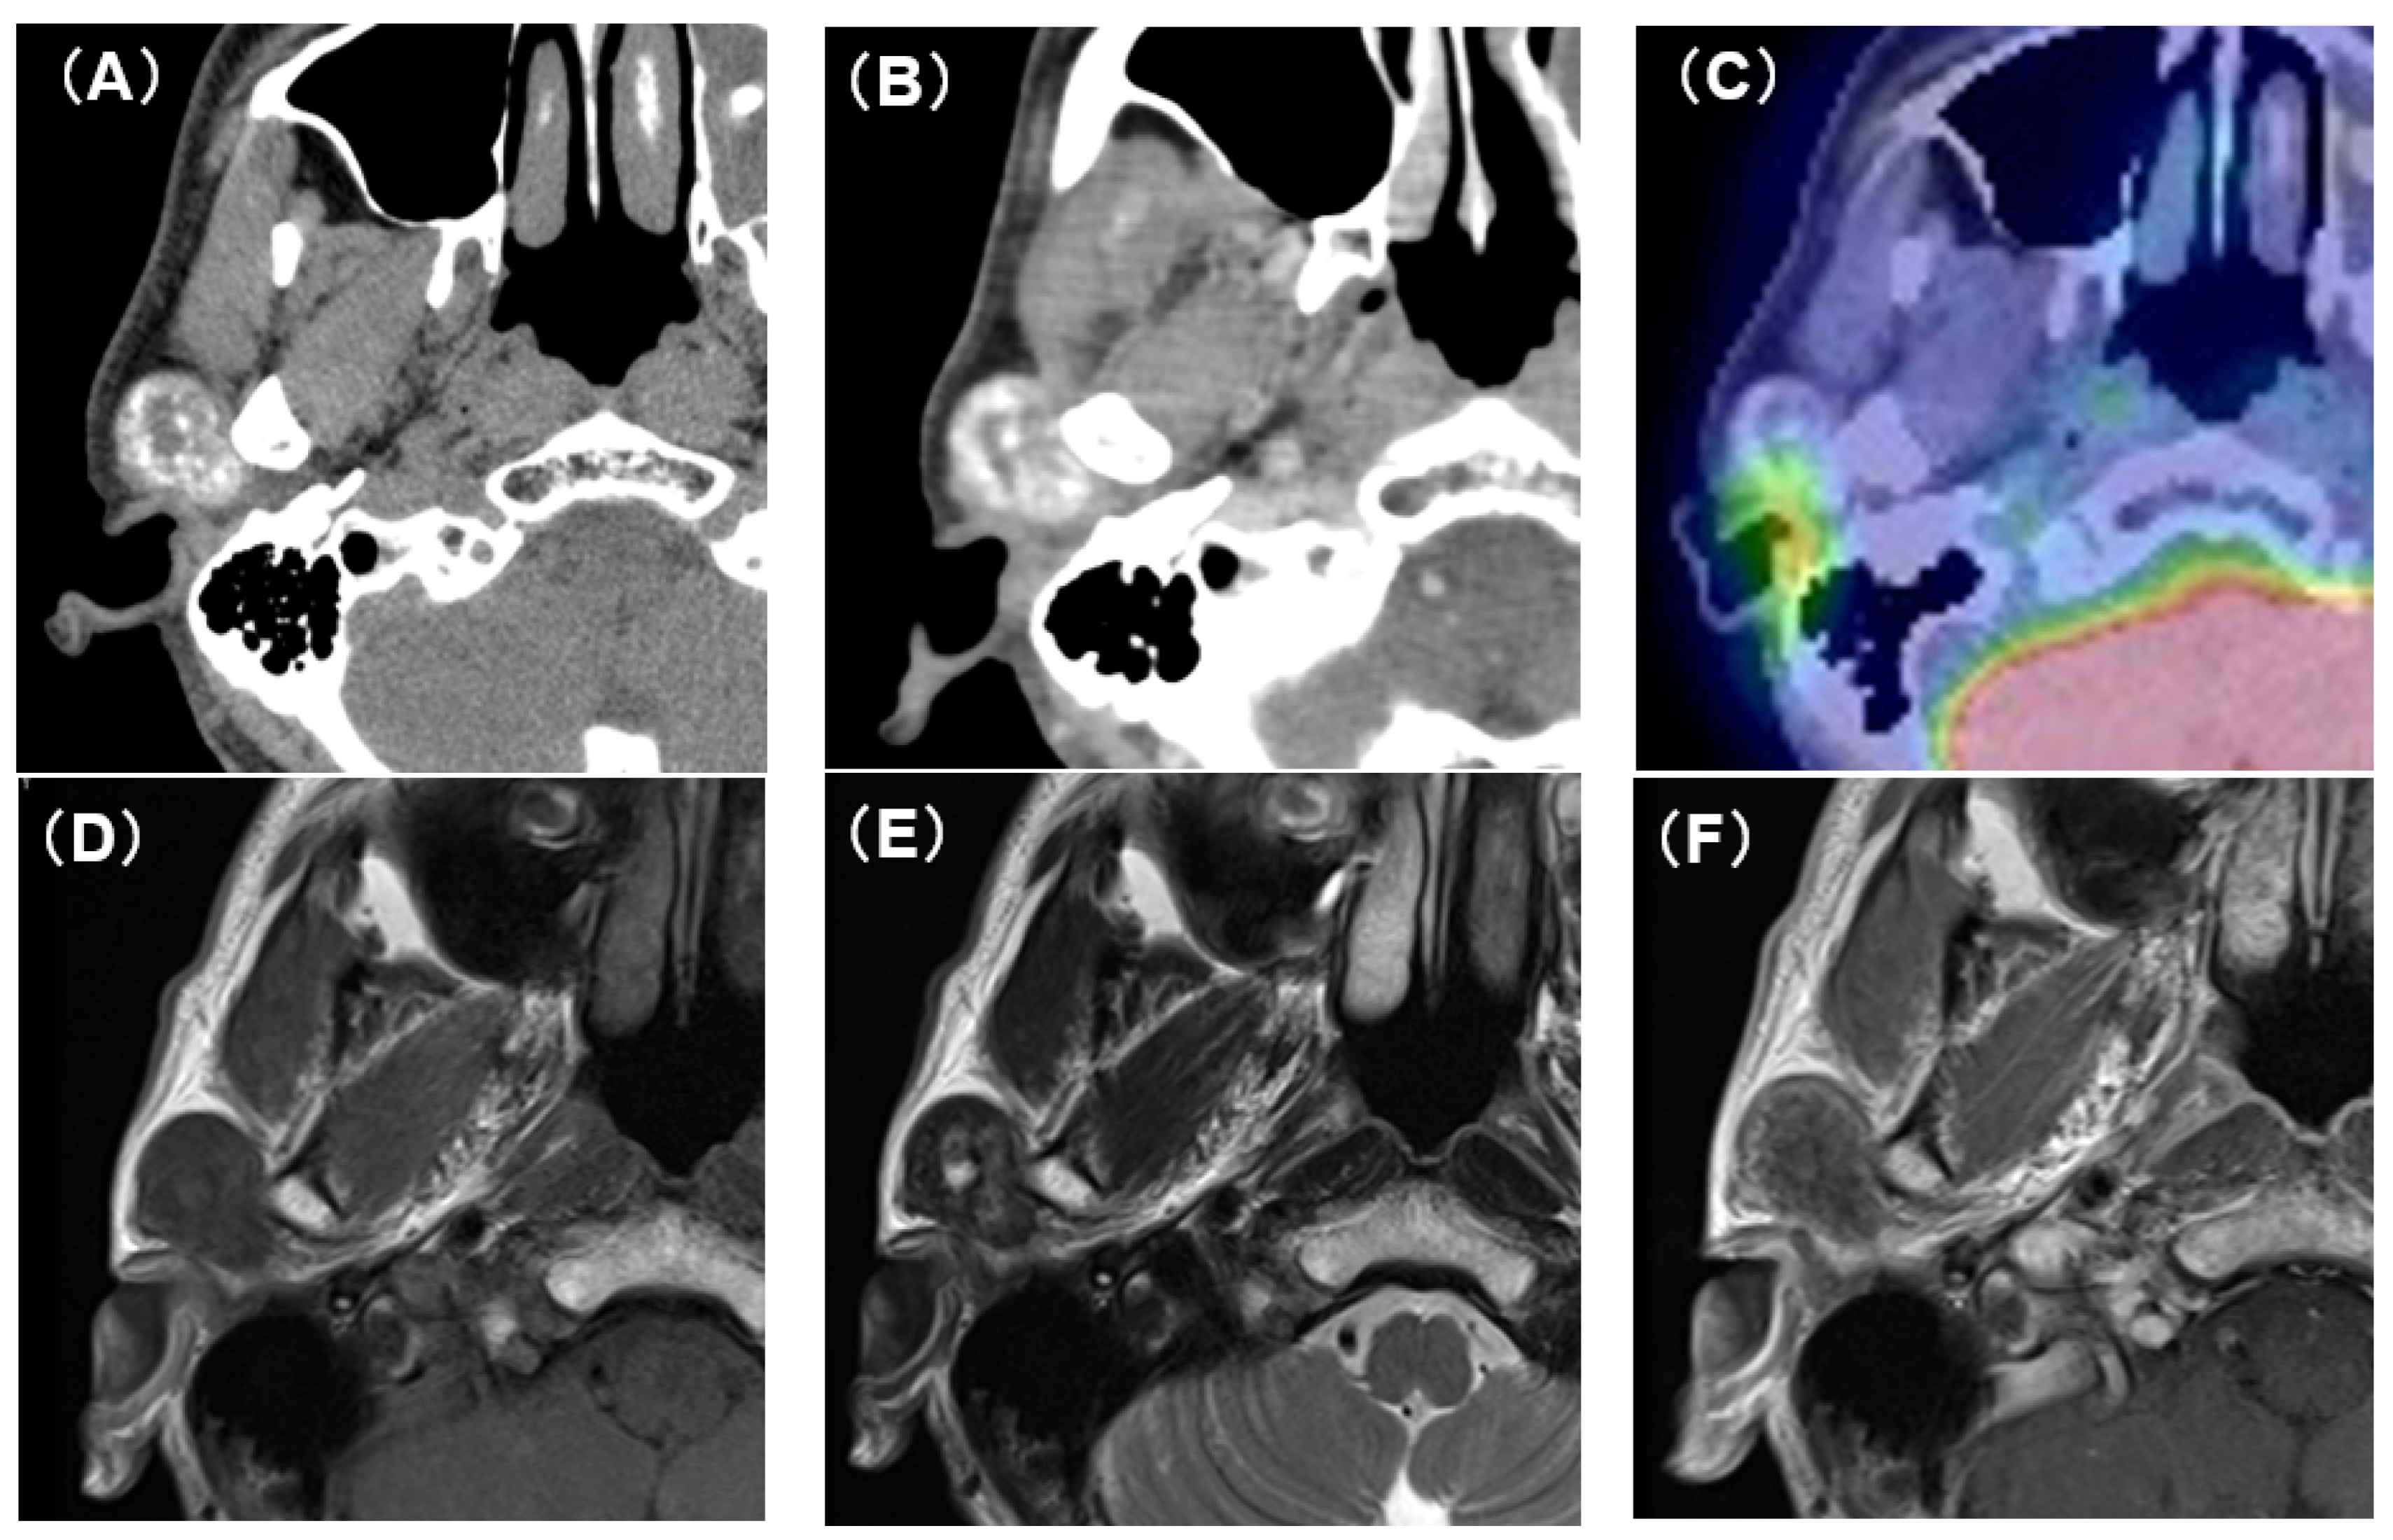

Computed tomography (CT) showed an oval tumor in the region of the right TMJ, extending to the upper pole of the parotid gland. The tumor was oval-shaped with an actual width of 2.5 cm and a length of 3 cm. It had well-defined borders and a diffuse hyper-absorptive zone within, which indicated diffuse calcification (Figure 1A,B). Positron emission tomography with 18F-fluorodeoxyglucose (18F-FDG-PET) showed a mild uptake of 18F-FDG (SUVmax = 3.25) (Figure 1C). There was no uptake in other sites except for physiological uptake. The tumor showed a poor contrast effect with iodine-based contrast medium. A magnetic resonance image (MRI) showed a well-defined mass in the upper pole of the right parotid gland. T1-weighted images showed a low-signal tumor (Figure 1D), while T2-weighted images showed a low-signal tumor with a macular high-signal area (Figure 1E). The contrast effect of gadolinium was poor (Figure 1F). Fine-needle aspiration cytology confirmed only neutrophils and histiocytes; there were no definitive findings.

Figure 1. CT, PET-CT, and MRI findings. (A) Plain CT horizontal section. The inside of the tumor is diffusely accompanied by a high-density area. (B) Contrast-enhanced CT horizontal section. The contrast enhancement effect of the tumor is poor. (C) PET-CT image findings. The tumor showed mild uptake of 18F-FDG (SUVmax = 3.25). (D) Plain MRI T1 image findings. The tumor is visualized as an area of uniform low-intensity. (E) Plain MRI T2 image findings. Low-intensity mass lesion with faint patchy hyperintensity inside. (F) Contrast-enhanced MRI T1 image findings. The tumor enhancement with gadolinium was poor.